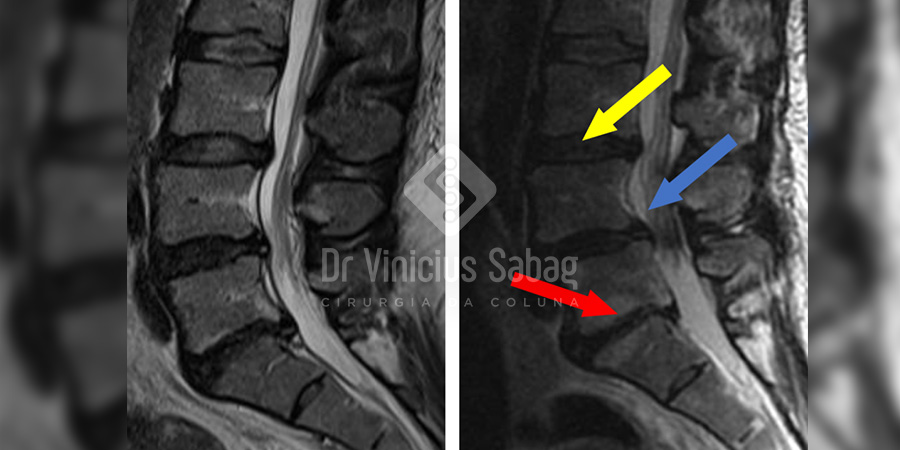

Abaixo, é possível visualizar claramente a evolução do quadro dessa paciente ao comparar as imagens de ressonância magnética realizadas em 2022 e em 2025.

Na imagem da esquerda (2022), observamos alterações iniciais, características de um processo degenerativo em estágio leve, com boa possibilidade de controle e estabilização com o tratamento adequado.

Já na imagem da direita (2025), nota-se uma piora importante da discopatia L5-S1 (seta vermelha) e o surgimento de desidratação discal L3-L4 (seta amarela).

Além disso, observamos sinais de instabilidade vertebral com o aparecimento de espondilolistese L4-L5 (seta azul), quadro que trouxe impacto direto na qualidade de vida da paciente e exigirá abordagens terapêuticas mais complexas.